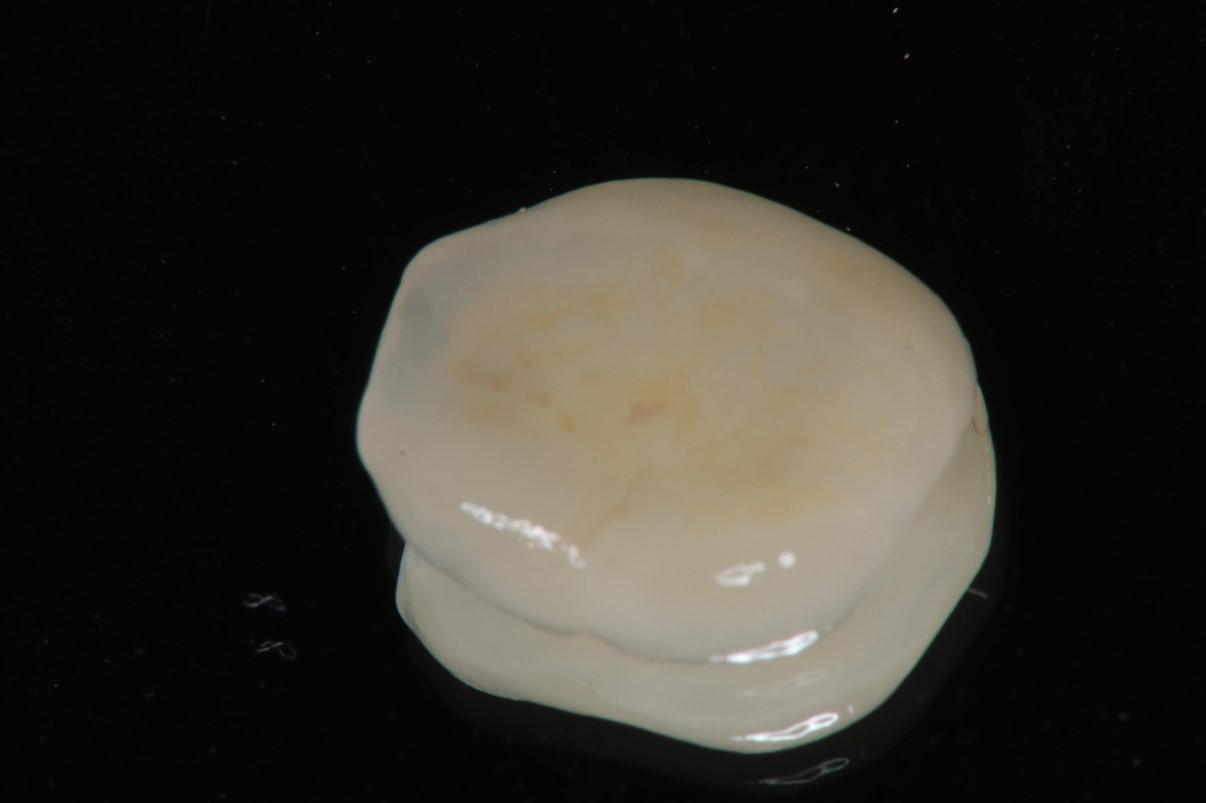

陶瓷冠塊體